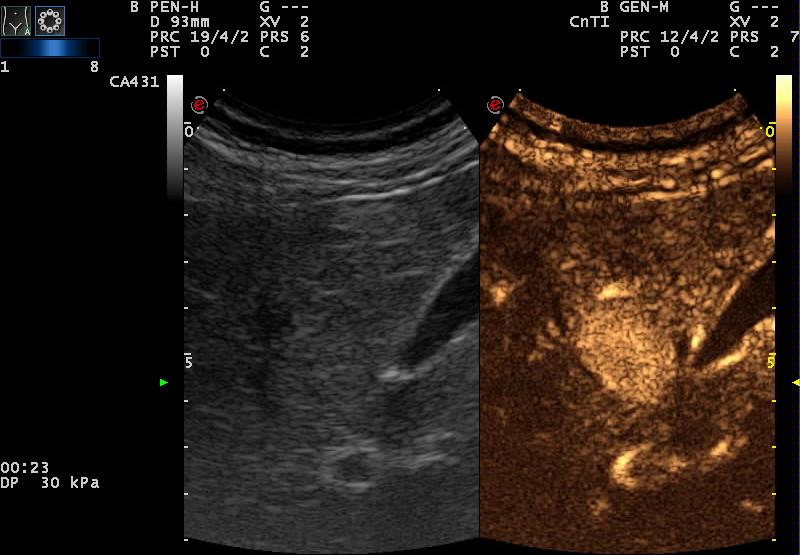

| B-képen isoechogén, korai artériás halmozás kontrasztanyagos UH-vizsgálattal |

| ua |